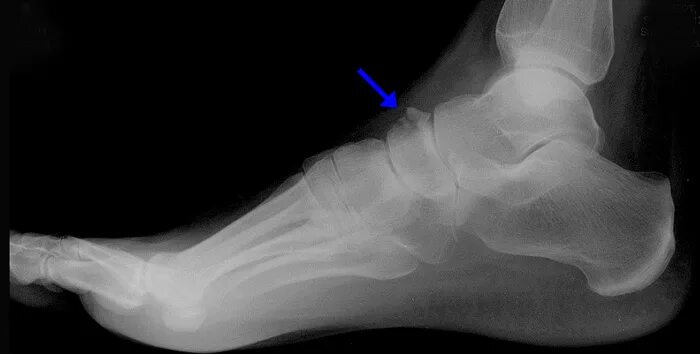

Перелом задней кости стопы